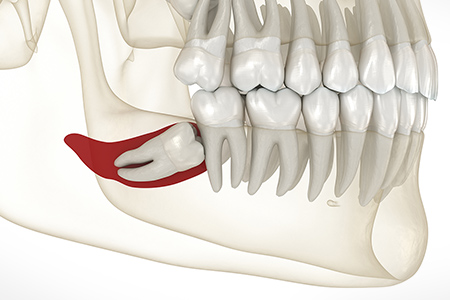

矯正治療では、親知らずは単純に歯並びを並べるために必要ない歯として抜歯されることが多々あります。しかし、赤坂B&S歯科・矯正歯科の位置づけでは、状態が悪い他の歯を積極的に抜き、親知らずを活用することで健康な歯を残すことが可能です。この場合状態が悪い他の歯の位置づけは、むし歯治療による歯のダメージや歯の神経を取った歯のことを言います。歯が並ぶ隙間が十分ある場合や、工夫によって隙間を作ることが可能な場合には抜歯は不要です。治療計画を決定する際には、正確な診断と治療法のメリット・デメリットを患者さんと共に検討し、適切な選択を行うことが重要です。

歯の移植とは、患者さんのお口の中にある使われていない歯、例えば親知らず(第三大臼歯)などを利用して、失った歯の場所に移植する歯科治療法です。これを「自家歯牙移植」と呼びます。ご自身の歯を使うため、親和性が高く、異物反応のリスクが低く、移植した歯が成功すれば、自然の歯と同様に機能します。

2. 親知らずの活用:親知らずが健全であり、かつ適切な位置に生えていない場合

移植する歯(例えば親知らず)を慎重に抜歯します。